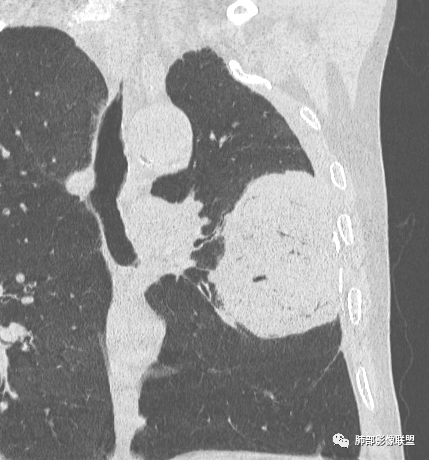

左肺上叶大肿块,膨胀性生长,边界清,密度较低,见部分坏死区,强化弱,肿块见支气管充气V扩张征,分布僵直,枯树枝特点,另一个重要特点血管造影征,淋巴瘤,肿块长轴与胸膜平行,与隐球菌鉴别,隐球荚膜抗原检查,明确诊断经皮肺穿刺。另胸膜钙化(问诊既往有无患胸膜炎病史)。

左肺上叶胸膜下肿块,宽基底与胸膜相连,跨叶裂,边缘清晰膨隆,其内支气管充气,部分扩张、僵直,无明显强化,血管造影征,考虑淋巴瘤,鉴别腺癌

左肺胸膜下巨大占位,跨叶裂,宽基底与胸膜相连,胸膜钙化,平扫密度较低,强化不明显,可见内部血管显影,支气管充气征和扩张,考虑为恶性,倾向于淋巴瘤

左侧胸腔巨大肿块,跨叶生长,临近胸膜钙化,边缘模糊,可见支气管影,定位肺内,增强后轻度强化,边缘见血管影,考虑淋巴瘤,鉴别肉瘤

左肺上叶胸膜下肿块,膨胀性生长,边界清晰,密度不均部分坏死,未见强化,病灶内支气管迂曲扩张,病灶长轴与胸膜平行,胸膜下脂肪间隙存在,胸膜钙化,考虑放线菌?毛霉?鉴别淋巴瘤

支持淋巴瘤,左上肺大肿块,有分叶,边缘光整,病灶内密度不均,可见支气管扩张征,增强后可见血管影征。周围肺野清晰。

左肺上叶肿块,宽基底与胸膜相连,跨叶裂,边缘清晰膨隆,可见小分叶,其内支气管充气,部分扩张、僵直,呈枯枝征,支气管达边征,增强无明显强化,可见血管造影征,考虑恶性病变,淋巴瘤,鉴别粘液腺癌。

大肿块,边缘光滑,深分叶

近端支气管堵塞、推移为主

部分类似于脐凹征

内部支气管扩张

肺动脉推移为主,边缘部分进入

大肿块、表面光滑但深分叶,肺门侧支气管堵塞

1)部位:周围型或中央型软组织肿块,以周围型为多见,且肿瘤多位于肺上叶。如本例:该肿瘤位于左肺上叶。

2)大小及形态:由于本病恶性程度高,早期症状不明显,发现时肿块均较大。如本例病变巨大。

3)肿块边界和边缘:多较清楚,呈圆形、类圆形,且由于肿块生长速度不均匀,可见分叶,毛刺少见。有报道肿块周围毛玻璃影是多形性癌特征表现。

4)密度:肿块平扫为软组织密度,由于体积较大,内部常见大片状坏死,可出现不规则厚壁空洞或坏死内多发无壁小空洞,坏死多不均匀:坏死灶内可见如柳絮样的斑片样强化灶,坏死边缘与非坏死区分界不清本例坏死较明显,密度不均匀。

5)肿瘤强化方式:肺部恶性肿瘤强化程度与其血供丰富程度相关,血供丰富多强化明显,反之则较差。由于PSC 周边实性部分富血供及内部黏液变性、坏死,增强后肿块多数呈轻-中度边缘环形强化或不均匀小斑片状强化。国外学者对照病理发现肿瘤细胞或胶原组织增强扫描时强化,无强化的低密度区代表了黏液样变性区和出血坏死区。